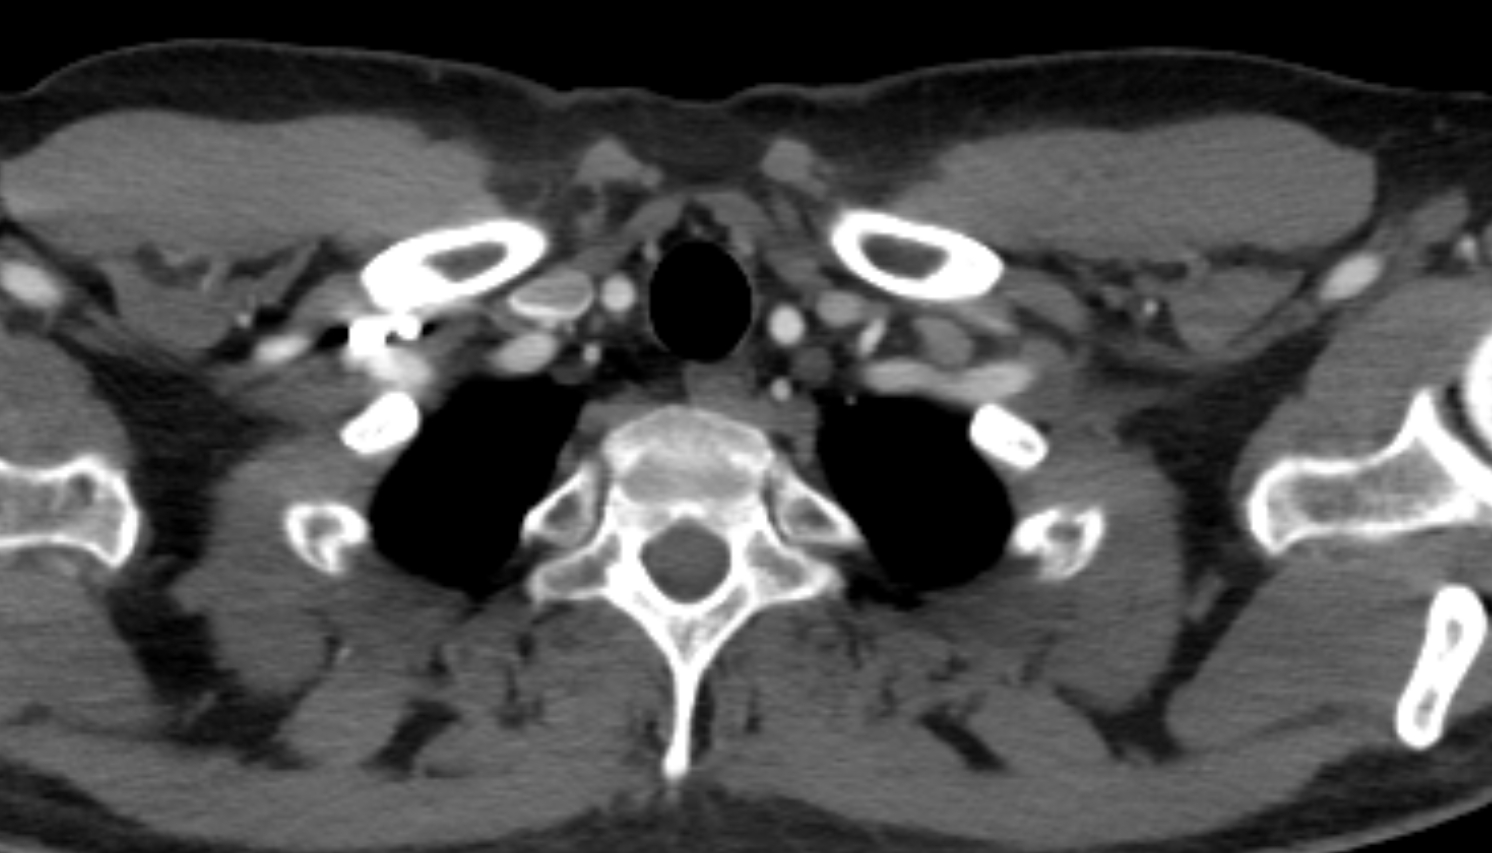

- Internal carotid artery (cervical part)

- Common carotid artery

- Carotid bifurcation